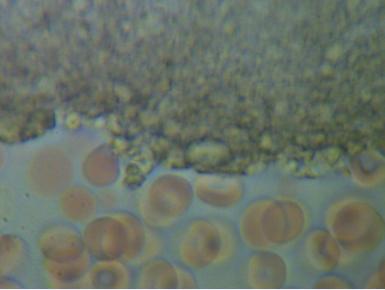

2.PASOŻYTY I GRZYBY

w zakwaszonym środowisku rozwijają się różnego rodzaju organizmy pasożytujące : robaki, grzyby, bakterie, wirusy i inne. Walka z nimi jest możliwa tylko przez zmianę środowiska z kwaśnego na zasadowe, w tym środowisku nie mogą się one rozmnażać i żyć.

We krwi widoczne są larwy i jaja pasożytów.

Komórki grzybów. W zależności od tego w jakim stopniu organizm zaatakowany jest przez grzyba widoczny jest obraz pojedynczych komórek lub całych kolonii i wtedy możemy mówić o bardzo niebezpiecznej dla organizmu grzybicy.